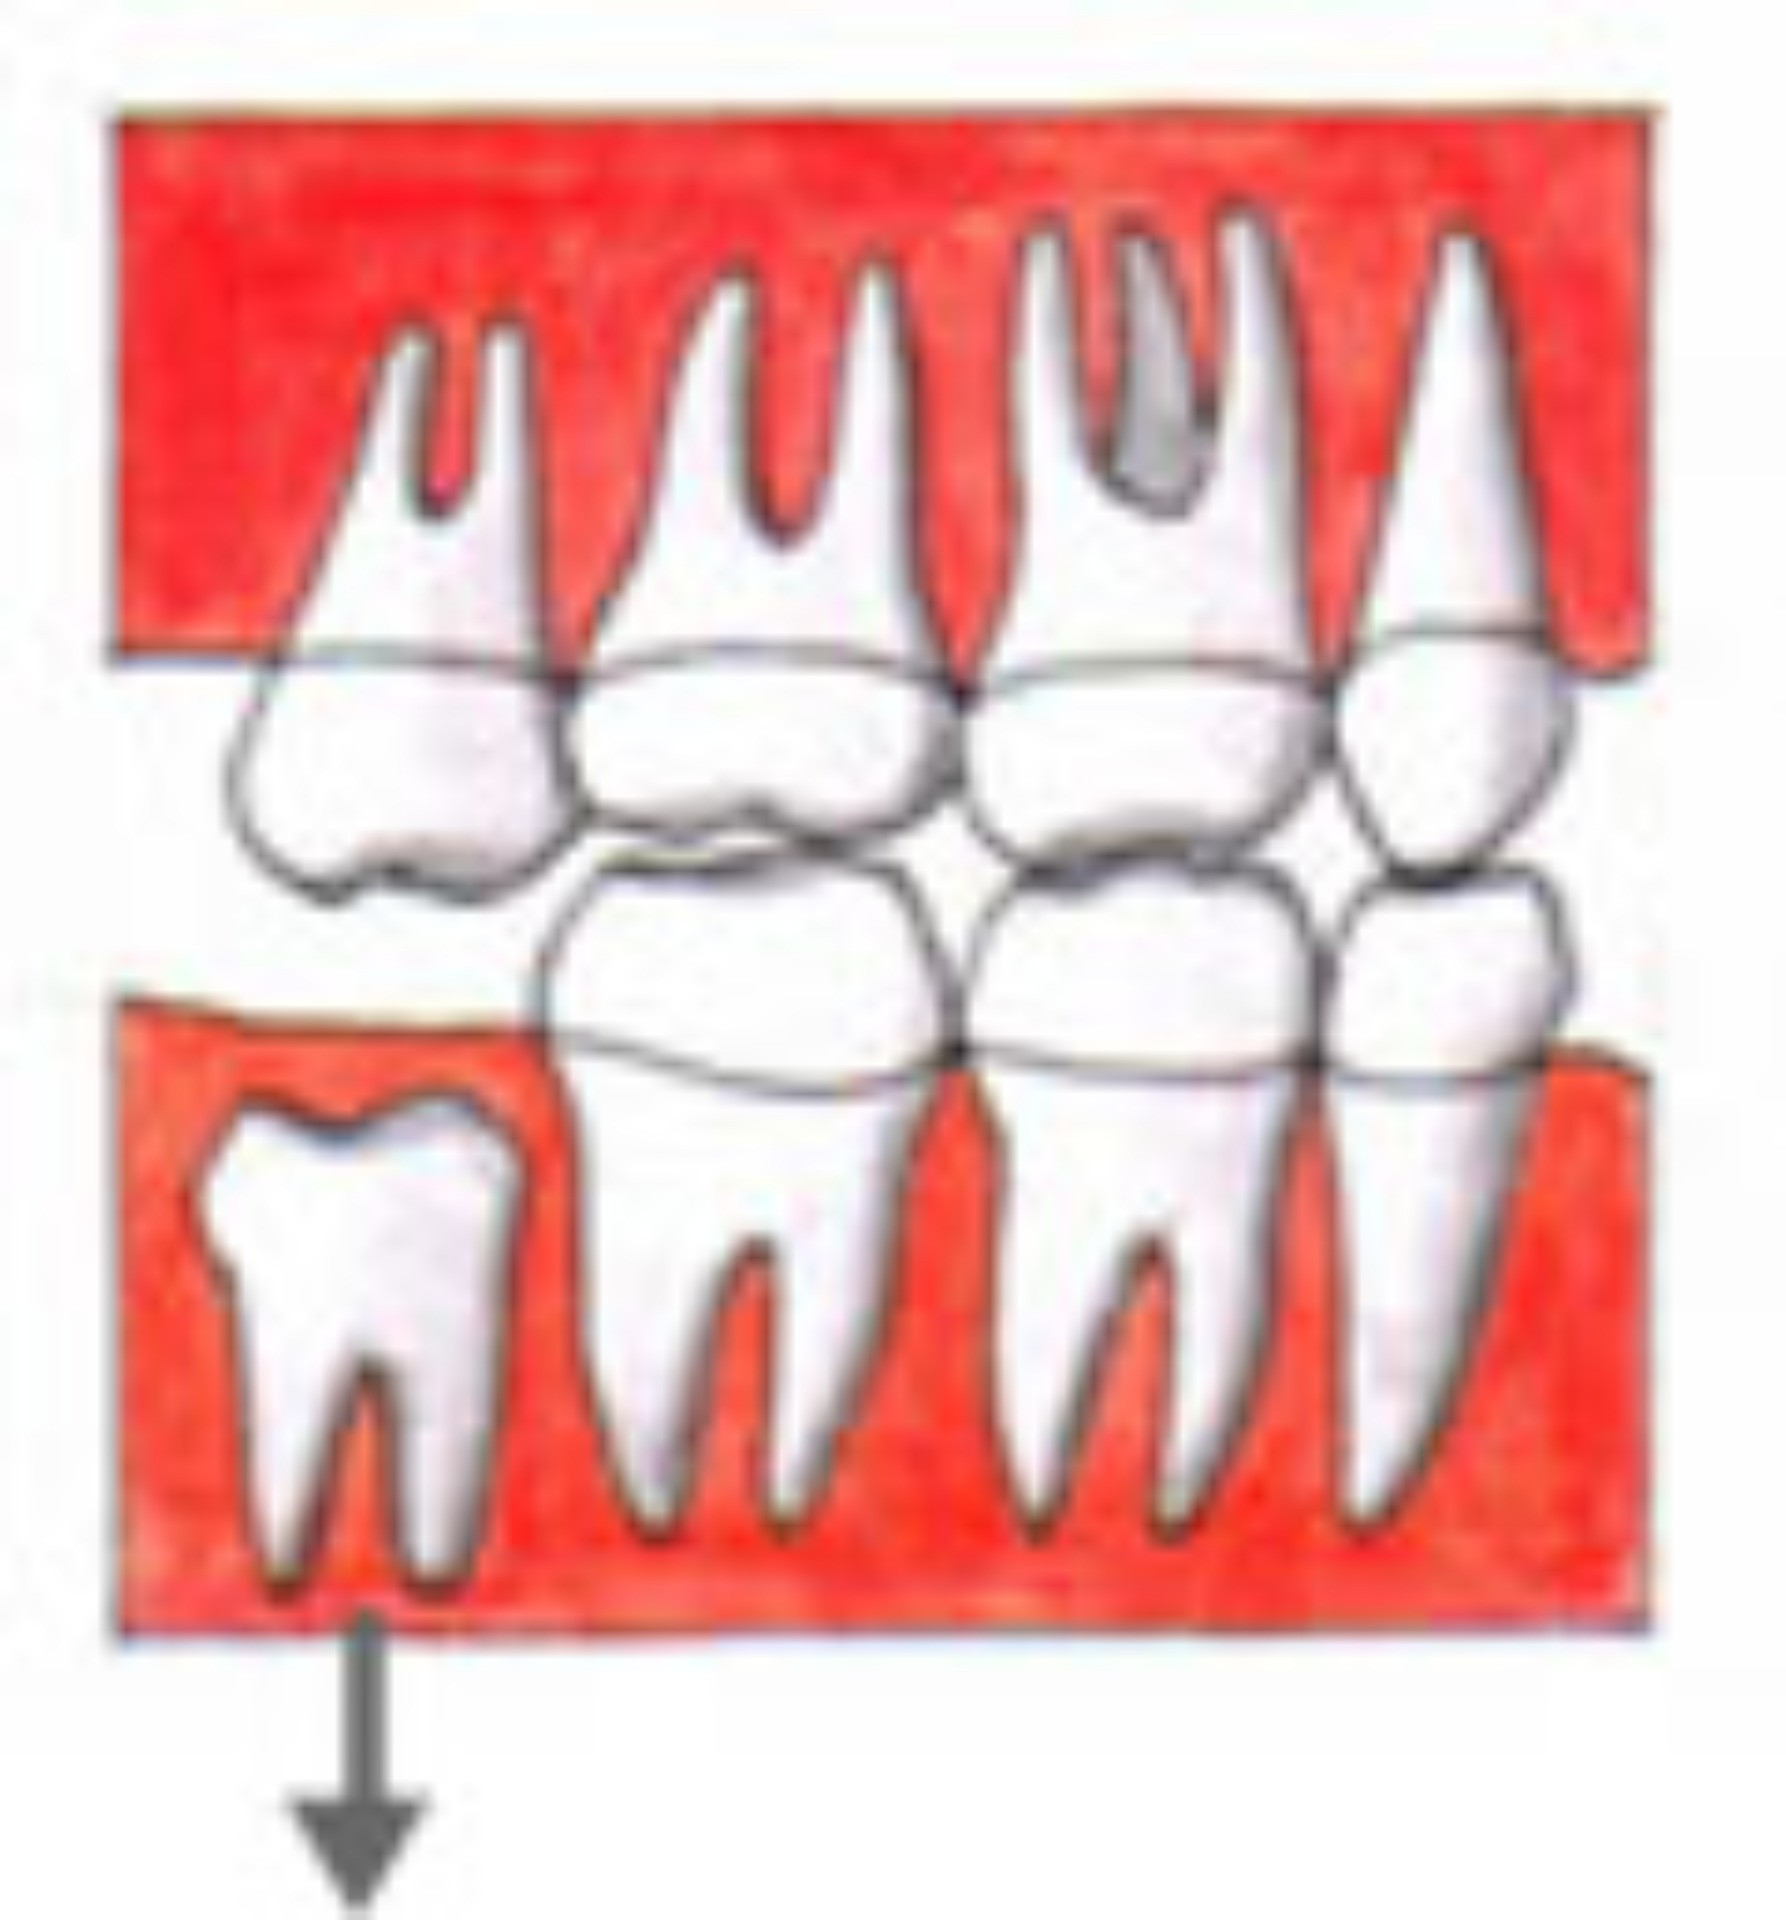

現代の人のアゴの骨は進化して小さくなってきています。しかし、歯の大きさは昔の人とあまり変わってはいません。ですから、最後に出てくる「親知らず」は、出てきたくてもスペースが狭く、正常には出てこない場合が多いのです。 下に挙げる図のように、一部分だけ頭を出しているだけであったり、斜めに傾いて出たり、アゴのなかで水平になったままのこともあります。 |

水平になっている 親知らず |

一部だけ出ている 親知らず |

上下の親知らずで歯肉を噛んでいる |

また、下の親知らずが正常に出てこない時、上の親知らずは正常であっても、上下がしっかり噛み合っていないため、どんどん上の親知らずが下がってきて、下の歯肉に当たるようになります。 本来、歯はなるべく抜かずに残したいものです。しかし親知らずに関しては、残しておいて悪いことはしても、いいことは何もないのです。